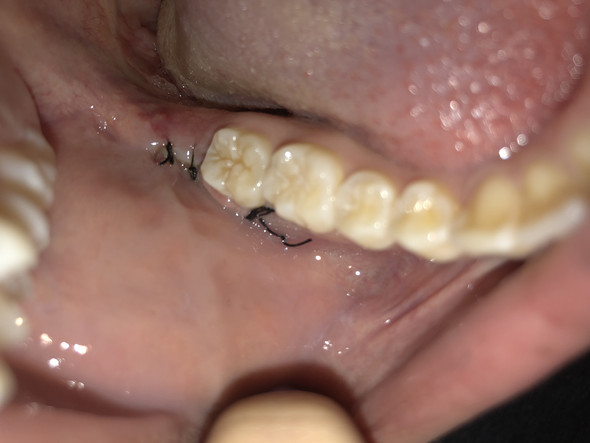

Die Fäden werden normalerweise nach 7 bis 10 Tagen entfernt. Du kannst nach einer Weisheitszahn-OP in der Regel nach 24 Stunden wieder Schokolade essen.2022 06:00 Uhr. Ob nach einem Schnitt mit dem Küchenmesser . 30 Minuten auf ein Tuch oder auf eine Kompresse zu beißen.Lebensmittel, die die Wundheilung im Mund fördern. Wenn du Schmerzen oder Schwellungen nach der Operation hast, solltest du deinen Zahnarzt kontaktieren und dich erkundigen, was du tun kannst, um es zu lindern.Wir empfehlen dir, die Kompressen mindestens die ersten zwei bis drei Tage nach der Verletzung anzuwenden.Weisheitszähne: Schmerzen, Symptome und Ablauf der OP. Dabei gibt es in der Regel keine .Nach einer Weisheitszahn-OP sollte man mindestens 48 Stunden warten, bevor man wieder Kaffee trinkt, um die Heilung nicht zu beeinträchtigen.